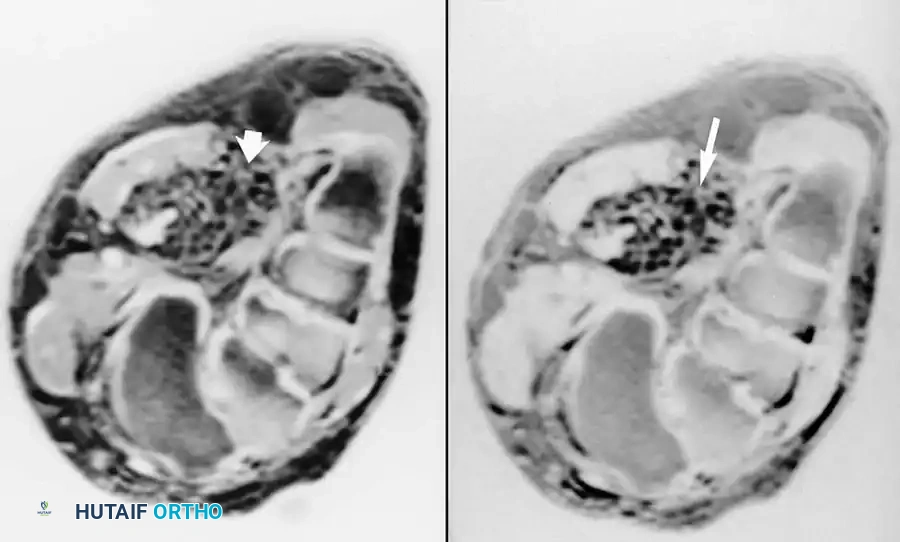

يعاني المريض من ألم شديد وتورم في الجزء الخلفي من الكوع، مع عدم القدرة على فرد الذراع ضد المقاومة. يؤكد الرنين المغناطيسي التشخيص من خلال إظهار انفصال الوتر عن مكان اتصاله بعظمة الناتئ الزجي في الكوع، مع وجود سوائل تملأ الفجوة بين الوتر والعظم.

أشعة الرنين المغناطيسي تظهر انفصال وتر العضلة ثلاثية الرؤوس عن عظمة الناتئ الزجي